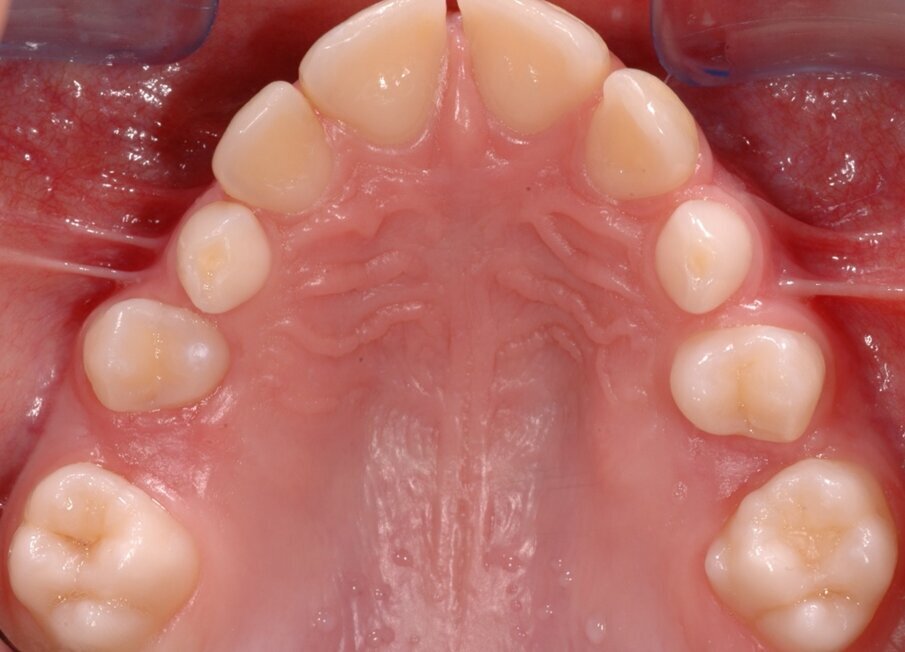

È importante ricordare che la lesione traumatica e/o cariosa può essere responsabile di patologie ascessuali e della perdita precoce di spazio in arcata, influendo negativamente sulla formazione e sull’eruzione del corrispondente elemento permanente. Necessario, pertanto, prevenire e curare tali evenienze, anche qualora si debba intervenire con trattamenti endodontici su elementi della serie decidua, affinché mantengano la propria integrità anatomica fino al completamento della permuta. Per eseguire un adeguato trattamento bisogna tenere in considerazione delle sostanziali differenze anatomiche e strutturali esistenti tra dentizione decidua e permanente che condizionano le situazioni patologiche del bambino. Le corone hanno una forma panciuta e tozza caratterizzate da uno smalto più sottile con uno spessore uniforme e dentina meno spessa.

Il tipo di contatto, inoltre, che si stabilisce tra un dente e quello adiacente non è identificabile in un punto, come avviene tra i denti permanenti, ma è rappresentato da una superficie. L’anatomia pulpare si presenta ampia rispetto alle dimensioni coronali, con cornetti pulpari più pronunciati. Tutte queste variabilità anatomiche rendono gli elementi decidui facilmente esposti a trattamenti endodontici, in seguito a processi cariosi.

Il trattamento endodontico del dente deciduo comporta principalmente due procedure: la pulpotomia e la pulpectomia. Non è consigliabile eseguire degli incappucciamenti della polpa poiché dalla letteratura si evince che la percentuale di successo a lungo termine è minore rispetto a quelle che si ottengono nei trattamenti di pulpotomia. La pulpotomia è il trattamento endodontico più utilizzato negli elementi decidui che mostrano l’interessamento della sola polpa camerale in seguito all’esposizione accidentale di una porzione di essa dovuta a un processo carioso o a un trauma, purché il dente risulti asintomatico per i segni clinici di sofferenza pulpare e non presenti segni radiografici di lesioni periapicali.

Lo scopo di questo trattamento è di preservare la vitalità della polpa radicolare favorendo un processo di rizalisi fisiologica. La metodica prevede l’esecuzione di una adeguata anestesia, montaggio della diga di gomma ed asportazione di tutto il tessuto carioso. Qualora si verificasse l’esposizione accidentale di un cornetto pulpare si procede all’apertura della camera pulpare, asportazione della polpa camerale fino a giungere a livello degli imbocchi canalari, utilizzando delle frese montate su turbina sotto abbondante irrigazione, controllo dell’emostasi, utilizzando dei pellet di cotone sterili.